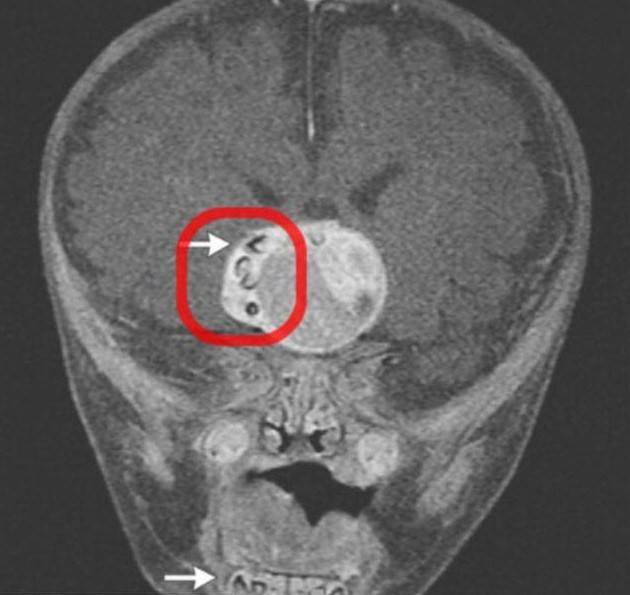

Cazul unic in lume care a luat prin surprindere lumea medicala. Dinte descoperit in tumoarea de pe creierul unui copil

Medicii au descoperit in creierul unui copil o tumoare ciudata. Cand au analizat-o in profunzime, au fost socati sa ...